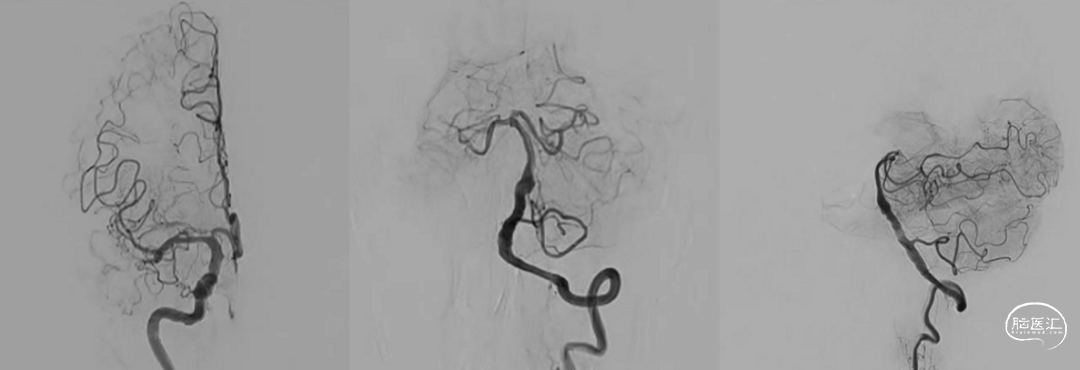

加奇SacSpeed® 2mm×9mm颅内球囊缓慢充盈成形扩张原位狭窄段;经球扩后,责任病变血管狭窄程度明显改善,前向血运流速改善。

责任病变血管管壁毛糙,内膜撕裂?血栓附壁?

欣维宁10ml静脉推注、6ml/h泵注20min,使用Wingspan 2.5mm×15mm颅内动脉支架定位于残余狭窄段释放。

推送加奇SacSpeed® 2mm×9mm颅内球囊至支架内后扩张成形(加奇SacSpeed® 2mm×9mm颅内球囊内加压至12atm)。

最后造影显示支架贴壁良好、支架内血运通畅、支架以远各级动脉分支显影良好。